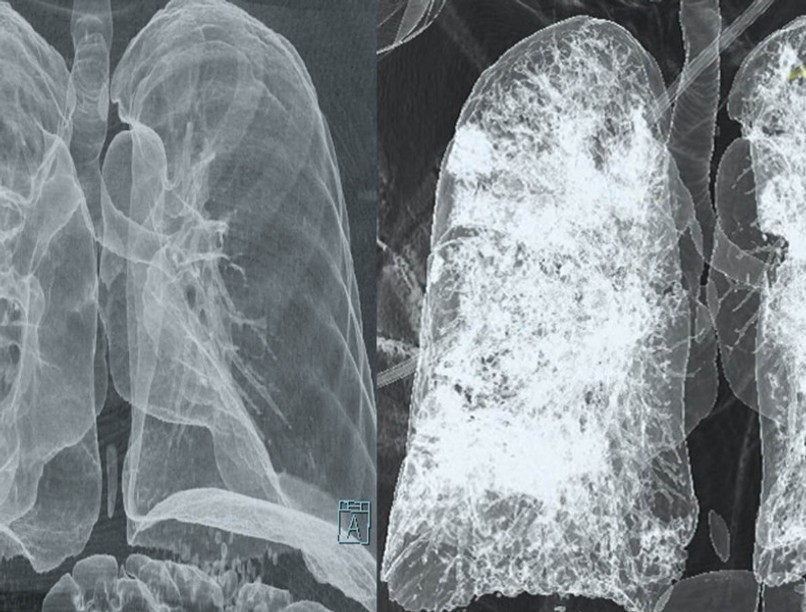

A tüdő CT (komputertomográfia) egy speciális képalkotó vizsgálat, amely részletes keresztmetszeti képeket készít a tüdőről és a környező struktúrákról. Ez a vizsgálat jóval részletesebb képet ad, mint egy hagyományos mellkasi röntgen, így pontosabb diagnózist tesz lehetővé számos tüdőbetegség esetén.

A mellkasröntgen egyszerűbb és gyorsabb vizsgálat, de kevésbé részletes. A CT sokkal részletesebb képet ad a tüdő szerkezetéről, így apróbb eltérések (pl. kis daganatok, gócok) is észlelhetők.